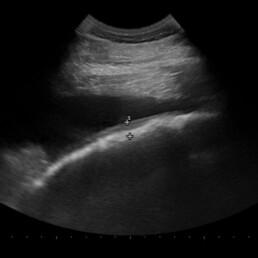

Weiterführende Untersuchungen: Ultraschall

- Magen physiologisch über drei Zwischenrippenräume darstellbar + runde Kuppel, gut abgrenzbar

- hier: Magenkontur über 6 Zwischenrippenräume darstellbar + Magenwand an Bauchwand anliegend

- Magen deutlich vergrößert